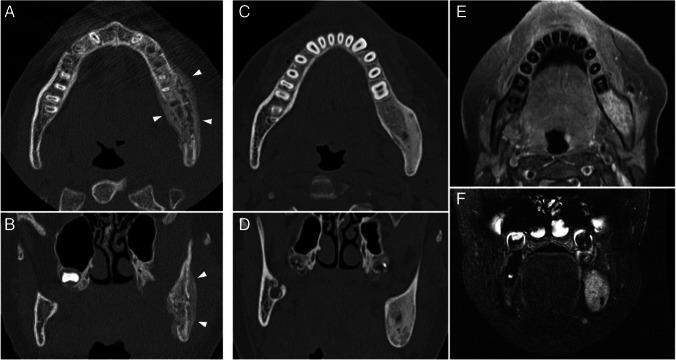

We included 13 patients (six male). The mean age of onset was 12.3 years. Ten patients had only vertebral lesions, two had only mandibular lesions, and one had both. For patients with vertebral lesions, the median number of levels affected was three, 81.8% had multiple levels affected, 90.0% had dorsal spine lesions, 72.7% had platyspondyly, and 81.8% had inflammatory changes. All vertebral lesions had at least partial resolution of inflammatory findings, the mean time of lesion activity was 2.5 years, and recurrence occurred in 27.3%. Three patients had sacral lesions, all with sacroiliitis. In patients with mandibular lesions, all had unilateral lesions involving the mandibular ramus, all had hyperostosis, periosteal reaction, bone edema, and soft tissue inflammation, all had partial resolution on follow-up, and one had recurrence.

CNO vertebral lesions are not rare, are often multiple, predominantly affect dorsal levels, and most result in vertebral height loss. Resolution of vertebral inflammatory lesions is frequent, but so is recurrence. Sacral lesions may be present and result in sacroiliitis. The mandible may be a site of unifocal disease, typically affecting the ramus, with prominent bony changes and soft tissue inflammation.

共纳入 13 例患者(男 6 例),平均发病年龄为 12.3 岁。10 例患者仅存在脊柱病变,2 例仅存在下颌病变,1 例同时存在两种病变。存在脊柱病变的患者中,受累椎体数中位数为 3 个,81.8%的患者存在多个椎体受累,90.0%的患者病变位于胸椎,72.7%的患者存在扁平椎,81.8%的患者存在炎症改变。所有脊柱病变均有不同程度的炎症改变缓解,病变活动的平均时间为 2.5 年,27.3%的患者复发。3 例患者存在骶骨病变,均伴有骶髂关节炎。存在下颌病变的患者中,病变均位于下颌骨升支,均表现为骨增生、骨膜反应、骨水肿和软组织炎症,随访时均有不同程度的缓解,1 例复发。

CNO 的脊柱病变并不罕见,常为多发病变,主要累及胸椎,且多导致椎体高度丢失。脊柱炎症性病变常可缓解,但也易复发。骶骨可能受累,导致骶髂关节炎。下颌可能为单发病变的部位,典型表现为升支受累,有明显的骨改变和软组织炎症。